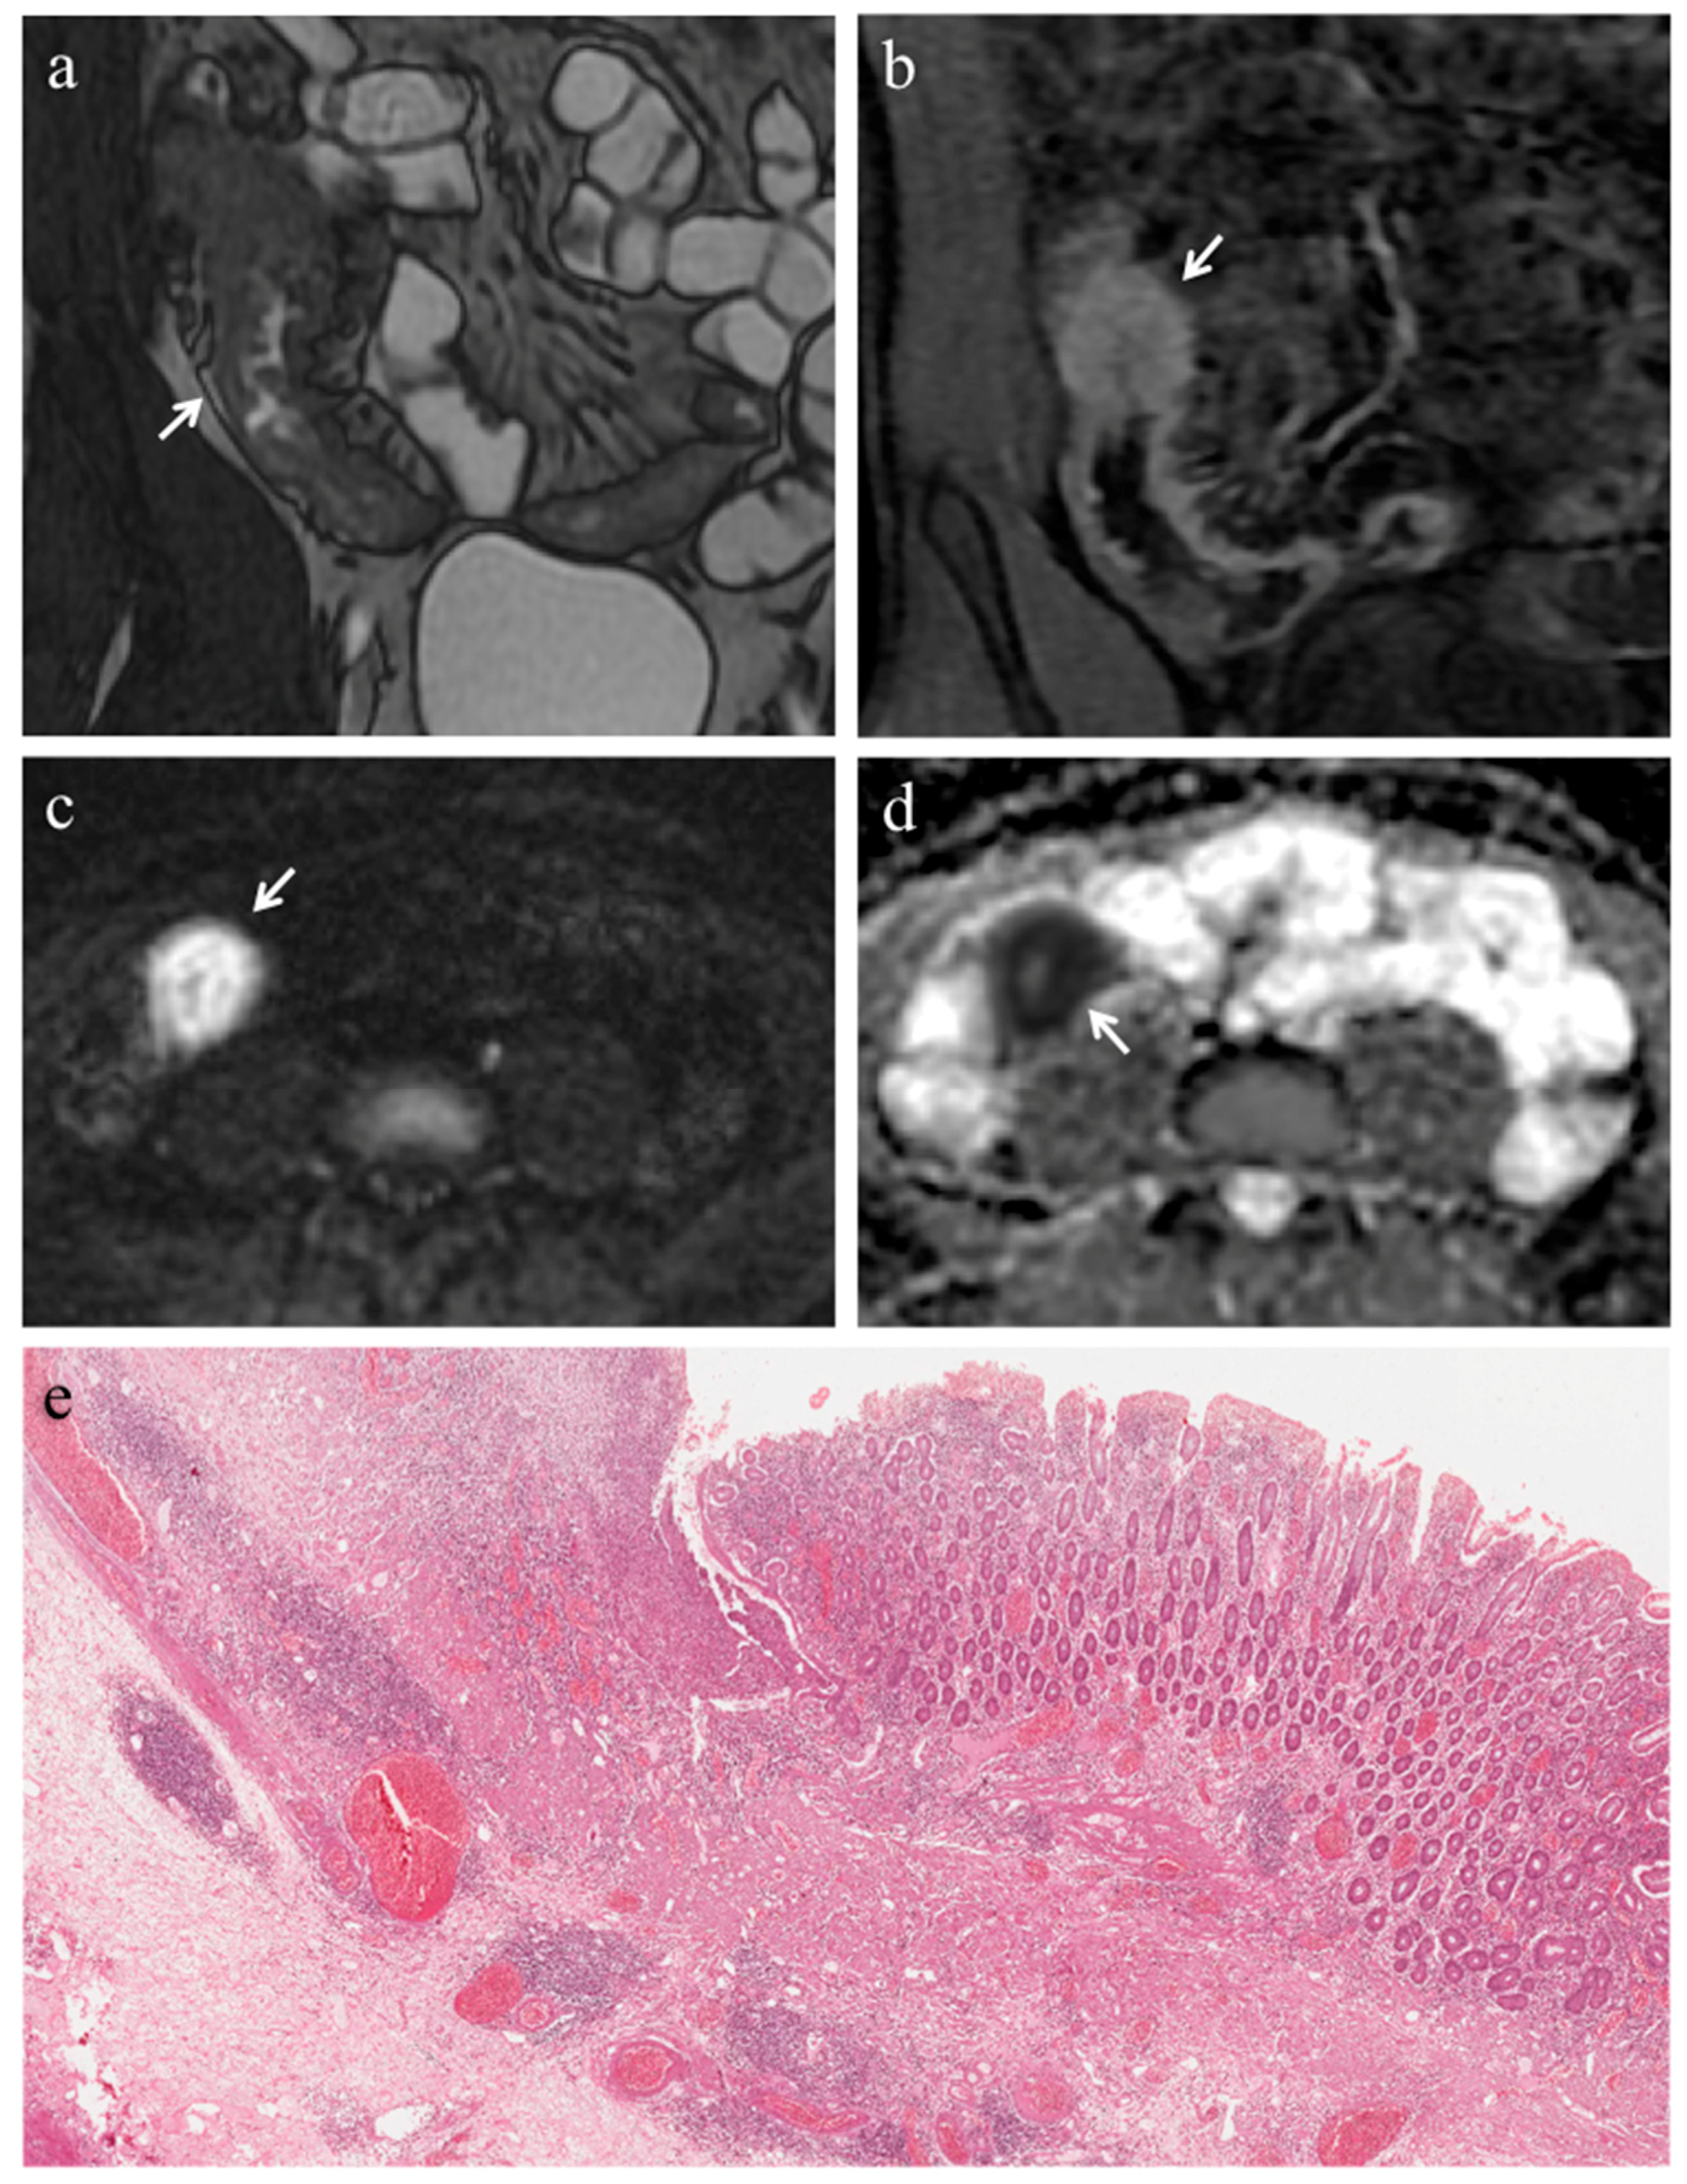

3.3. Analysis of Conventional MRE Sequences

3.4. Analysis of DWI Quantitative Measures (ADC)